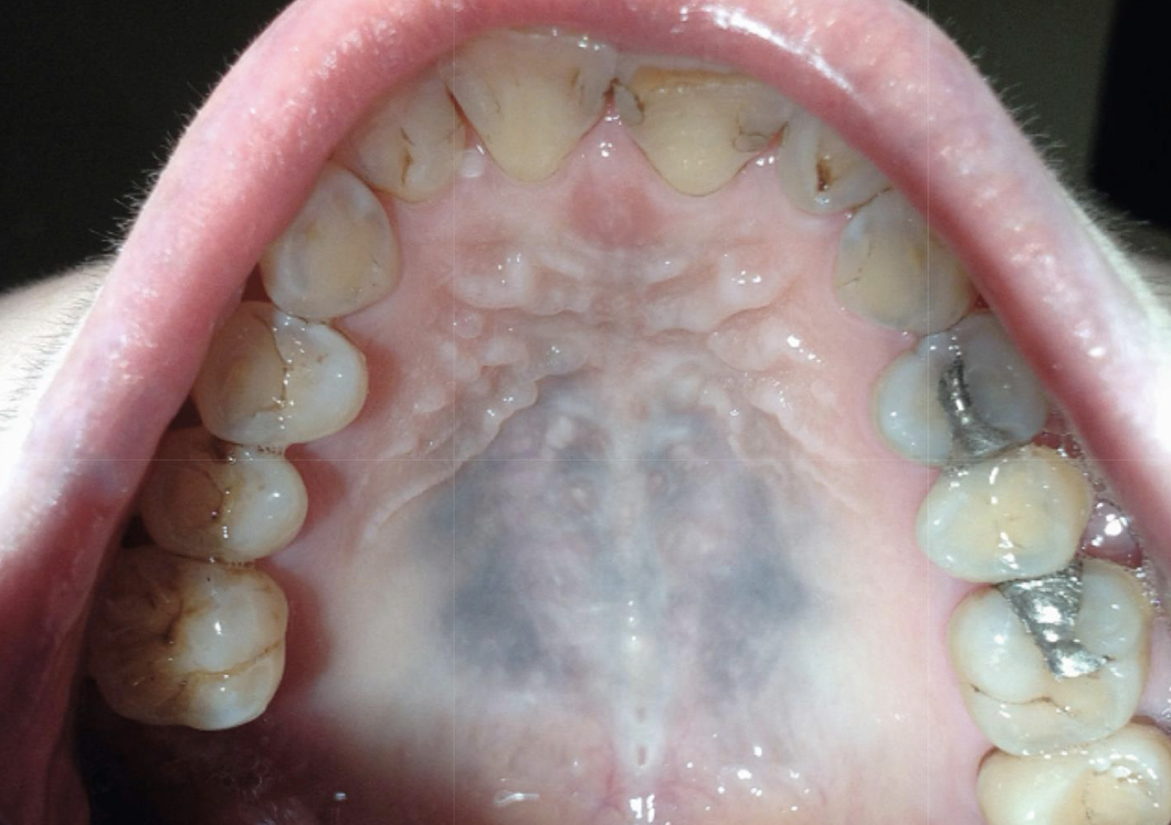

which pigmented lesion?

clinical features

Asymptomatic, localized

Blue-gray macule

Gingiva/alveolar ridge mucosa (50%)➔ buccal mucosa ➔floor of mouth

Localized around areas with: (blank) restoration

amalgam tattoo (exogenous, non-melanated)

amalgam tattoos appear where 50% of the time?

gingiva/alveolar ridge mucosa